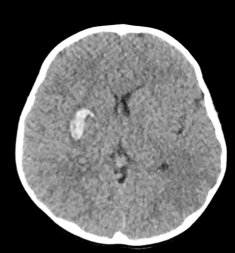

il existe également des micro-anévrysmes, rares chez l’enfant, pouvant être à l’origine d’une hémorragie ; il existe rarement des macro-anévrysmes liés à la perturbation du flux artériel.

- l’IRM : elle montre les lésions ischémiques et hémorragiques, la vascularisation de suppléance au niveau diencéphalique